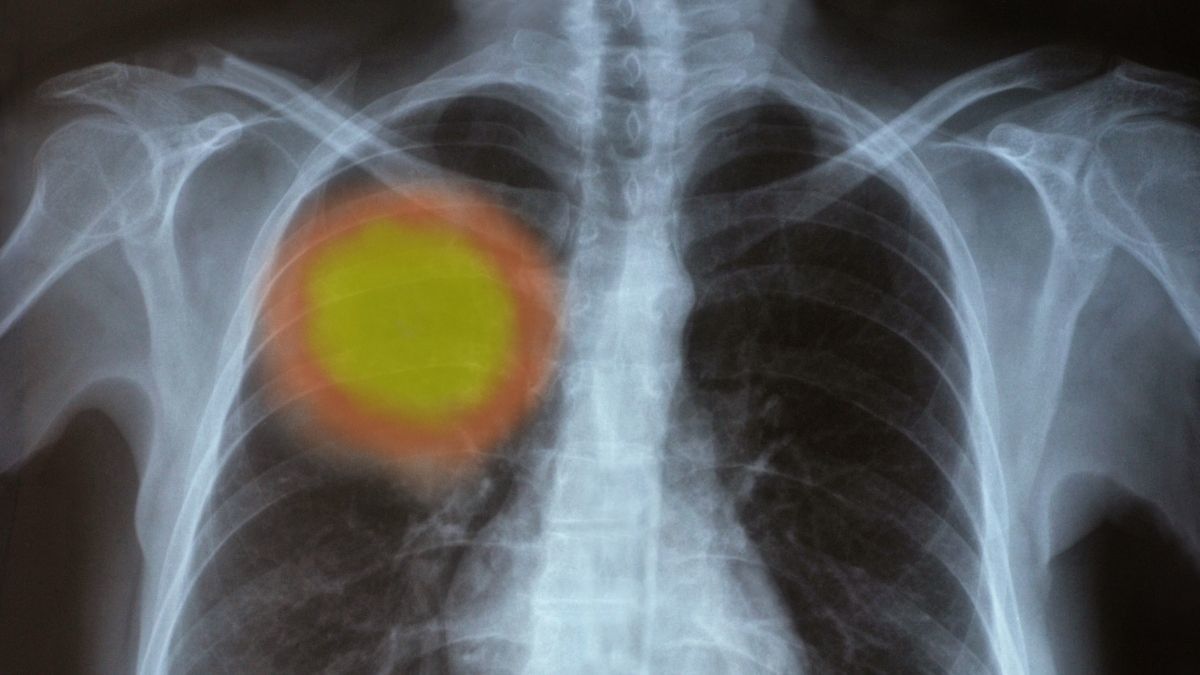

Komplikasi kanker paru-paru dapat muncul ketika stadium penyakit keganasan ini sudah tinggi.

Komplikasi dapat memperparah kondisi kesehatan paru-paru hingga menyerang organ tubuh lainnya. Berikut adalah komplikasi paru-paru yang harus Anda tahu.